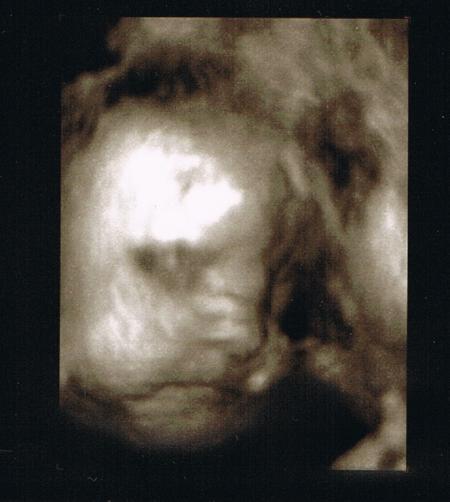

sehr schön und das bild ist süß....